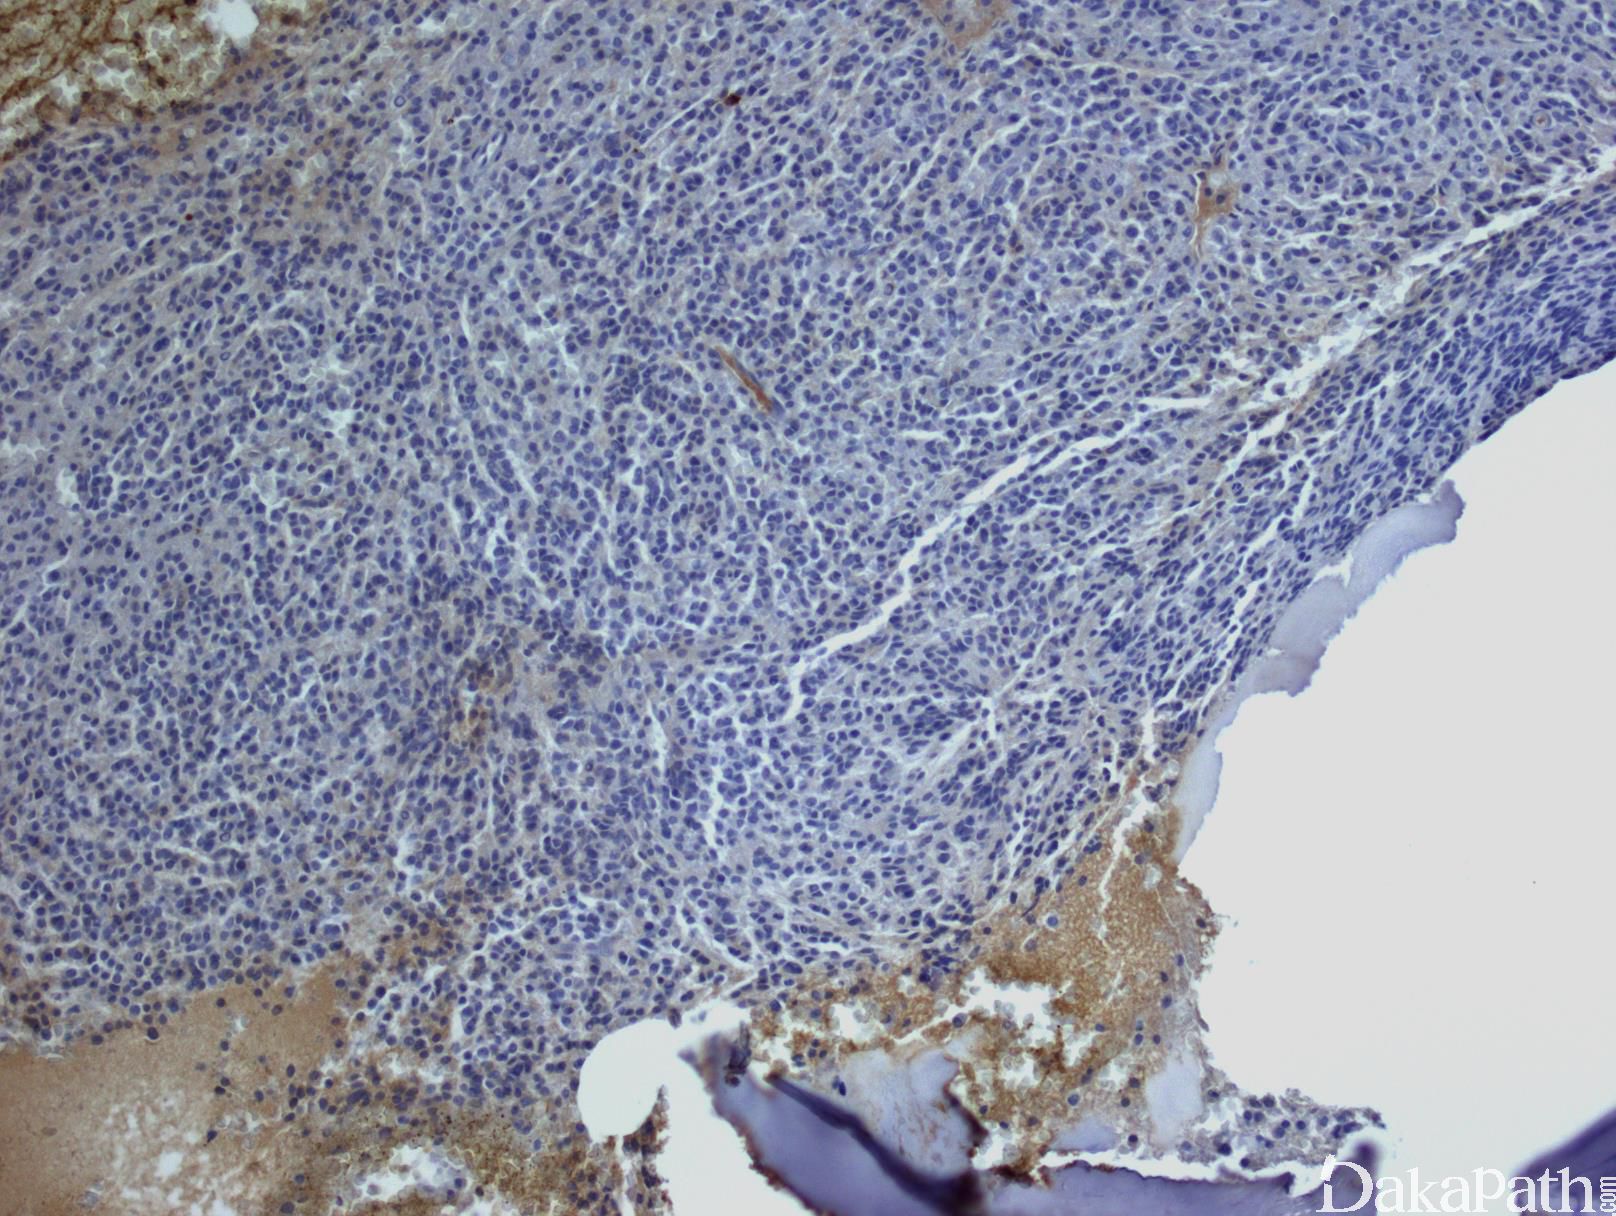

根据疾病的不同阶段,骨髓浆细胞浸润方式可以表现为间质性、局灶性或弥漫性浸润。一般浆细胞数达骨髓容量 30%,浆细胞骨髓瘤可能性很大。

肿瘤浆细胞形态变化很大,可以是成熟性、中间性、不成熟性、浆母细胞性或多形性。小细胞型则类似淋巴浆细胞,容易误诊为 LPL 或套细胞淋巴瘤。

浆细胞表达 CD138. 胞浆内 kappa 或 lambda,但无限制性表面轻链。CD19 和 CD20 一般阴性,但少数病例 CD20 有表达或部分表达。有些病例 cyclin D1+, 多见于类似淋巴浆细胞样形态的浆细胞骨髓瘤。异常表达的抗原(正常浆细胞不表达或仅少数细胞表达)有:CD56(见于 75-80%病例)、CD200(60-75%)、CD28(40%)、KIT(20-35%)、CD20(10-20%)。